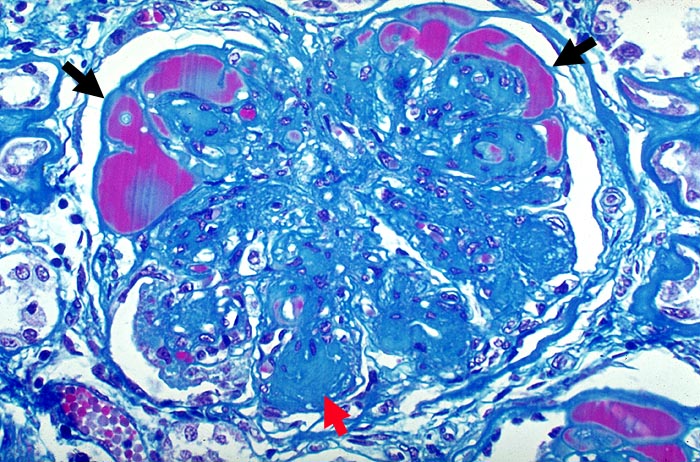

Noduläre diabetische Glomerulosklerose Kimmelstiel-Wilson

Die Mesangiumarelae sind knotig verdickt. Die Knoten zeigen eine angedeutete Schichtung. Die peripheren Glomerulusschlinge sind hochgradig eingeengt. In Gefässpolnähe werden sie von Proteinthromben ausgefüllt (Exsudative Läsion).